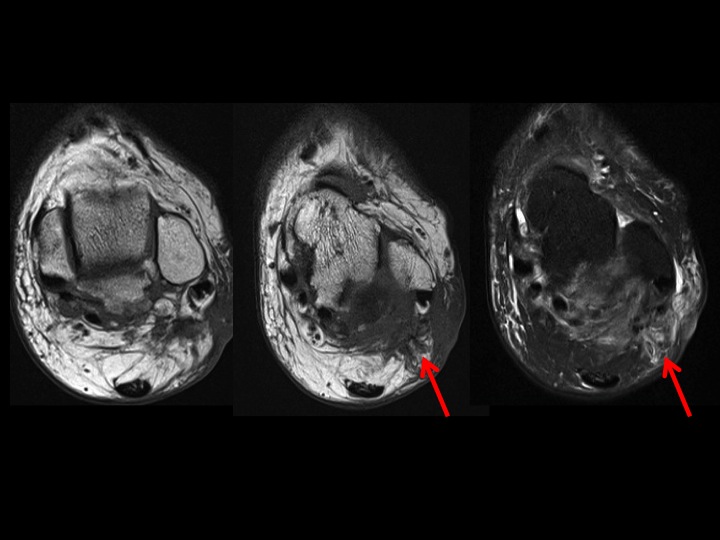

42 yr old female with 8 months burning lateral foot pain after ankle surgery

First 2 slides show an enormous os trigonum with posterior ankle impingement and associated FHL tenosynovitis. Latter 3 post op slides should extensive scarring obscuring fat planes in the region of the sural nerve which is presumably encased. Reference article.

sural nerve ( RID7347 )